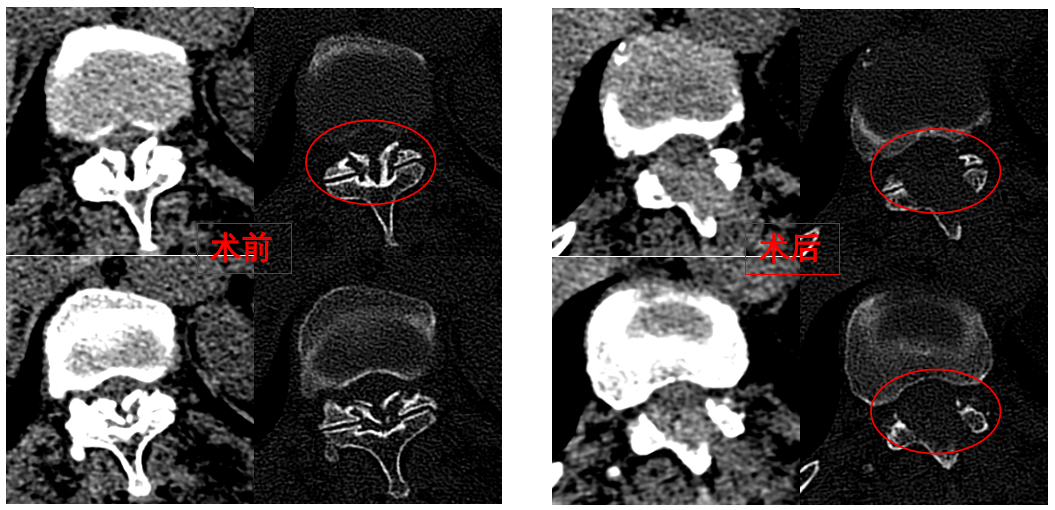

華西醫(yī)院成辦分院骨科副主任醫(yī)師張斌接診后,憑借豐富的脊柱治療經驗,立即安排卓瑪阿媽做了系列精密檢查,檢查結果顯示,阿媽胸椎11/12節(jié)段黃韌帶嚴重骨化,導致椎管顯著狹窄,脊髓受壓,確診為嚴重的“胸椎黃韌帶骨化癥”,如果不及時手術最終可能面臨癱瘓的風險。

手術歷時一個半小時,骨科脊柱微創(chuàng)團隊成功完整切除了壓迫脊髓的骨化黃韌帶,徹底解除了卓瑪阿媽的脊髓壓迫。手術過程順利,手術切口僅1厘米。

圖為卓瑪阿媽術前、術后胸椎CT照片對比。